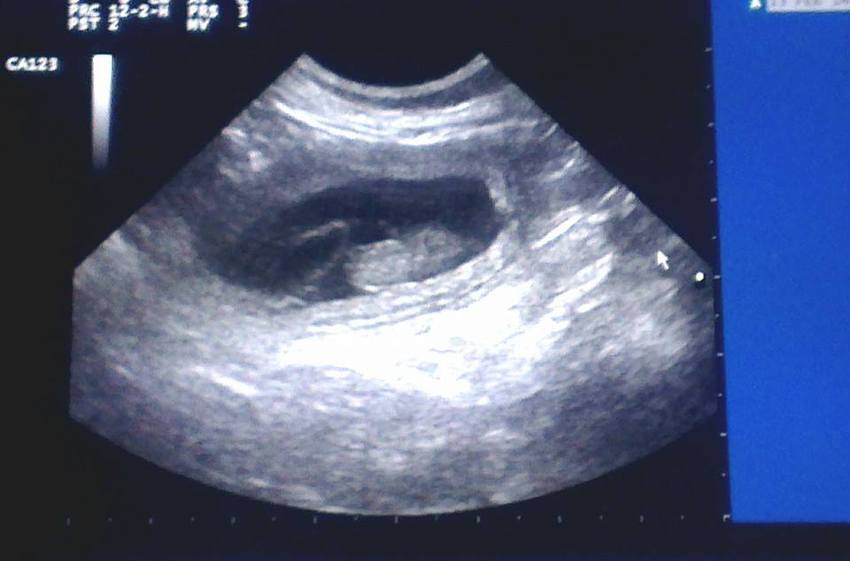

Met 29 dagen dracht hebben we een echo laten maken en daar was te zien dat we dit keer op een stuk meer als 2 pups kunnen gaan rekenen! Er is niet echt geteld maar er waren al 4 pups bijna tegelijk in beeld te zien en er waren nog wel wat meer te zien. Hoeveel blijft nog even een verassing

En wat foto's van de echo: